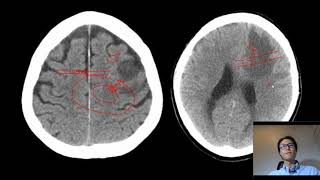

sub-regiões ali do desse bairro né do lobo frontal tá E para começar a escrever o lobo frontal eu vou começar aqui no plano axial e eu vou subir o corte olha só essa linha vermelha de referência Verde aqui no coronal eu vou lá no topo da cabeça tá eu vou lá no topo a Escort mais creais é que eu vou ter alguns Marcos anatômicos bem interessante Então o que que vai delimitar posteriormente quando os seus limites posterior do alto frontal vai ser o suco Central tá suco Central então aqui está o suco Central Existem algumas

dicas presente delimitar suco Central tá é existe umas dicas para experimentar esse suco Central é o primeiro é essa morfologia né então show apagar aqui Ah tá Se você reparar quando eu giro giro cortes né óleo eu dou uma virada aqui no corte axial o sucos Então essa é a morfologia que lembra a letra grega Ômega né agregar o homem é às vezes é uma letra grega meio de torcida é então chama e sinal aqui de sinal do Ômega invertido né porque a letra grega Ômega mais de de ponta cabeça mas depois cabeça deixar o

seu do gancho também que parece um gancho então via de regra esse sulco aqui que parece um a letra grega Ômega é o sulco Central o deixou escrevendo aqui no lado a as dicas da o pessoal consegui anotar então sinal do negar invertido outra dica a localizar os dois sucos aqui que tem uma orientação paralela né que são sucos pré e pós Central Então os esses dois dias Jesus pré e pós Central onde ficam parte importante das áreas motoras e sensitivas primárias eles têm uma orientação paralela né aqui no da superfície dorso lateral na convexidade

cerebral é e eles vão delimitar que o suco Central bom então esse aqui é outra dica colocar aqui para vocês os dois giros paralelos Oi hoje dos paralelos outra dica a gente pode procurar é o suco sem sulco frontal superior é esse suco aqui que ele corre no sentido longitudinal né e corre na direção aqui do maior maior eixo do creme e ele é um sulco longitudinal mais superior então sulco frontal superior ele via de regra e vai terminar no suco pré-central e vamos escrever aqui sou Goku frontal superior terminando só no suco pré-central e

para central não sei aqui tá tendo surpresa Central Sem que o próximo suco ao sulco Central portanto eu sei que aqui está o limite né posterior do sulco frontal aqui na superfície dorso lateral ou na complexidade cerebral é deixa eu apagar aqui vou trazer que a gente pode utilizar também é esse suco aqui o que fica tocando a superfície Medial dos hemisférios cerebrais a esta morfologia característica aqui ela é chamada é chamado sinal do Bigode né então fica parecendo bigode aqui no plano axial lá no topo da cabeça tem que ir lá na alta complexidade

ele que vai procurar esses pontos diferentes Então a gente tem o final do bigode do bigode de corresponde ao rapaz mais de nariz do suco do cio tá Não se preocupem para que não tá acostumado com esse esse tempo parece um palavrão né o nome que assusta um pouco mas é uma coisa que realmente simples que a gente vai ver daqui a a avaliar a superfície medial do lobo frontal frontal e parietal na verdade né então o que tem a paz marginais do suco docinho e qualquer dica que desses Nacional do Bigode é via de

regra o super centauri toca as a superfície Medial aqui do hemisfério cerebral né e o sinal do Bigode ou pais imaginários porção Marginal do sulco do cíngulo ele fica um pouquinho posterior em relação ao sulco Central Então quando você vai acompanhando aí o suco Central achou o sinal do Bigode o próximo suco logo à frente dele é o Central então eles têm todas essas dicas Porque é importante saber mais de uma dica é porque às vezes uma das dicas tá dos pacientes têm uma variação anatômica né Aliás o ômega por exemplo não tá com o

ômega assim tá o melhor meio torto fazer o suco Central na casa exatamente ali no super é Central Então é bom você sabia conhecer mais de uma dica né porque eles Uma delas pode notar não tá tá muito e Líder né E quando você tem uma lesão expansiva quando tem uma distorção do parênquima você tem esse conhecimento aqui né de todas essas dicas vai ser bastante útil para que mesmo você tem um deslocamento do suco central por uma massa por exemplo as relações anatômicas vão estar presente sustentável curso lá terminando do suco peça Central os